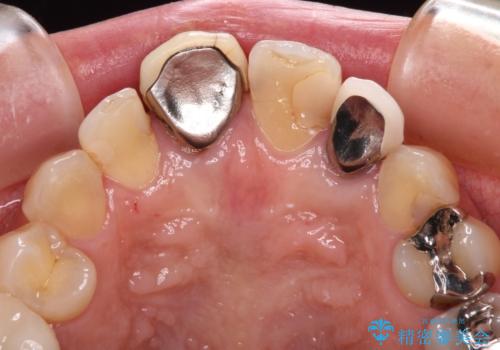

- 保険診療でのクラウンが変色してしまったとのことで来院された患者様です。

根管治療がされていなかったため、まずは根管治療を行い、その後オールセラミッククラウンにて補綴することとしました。

左上の歯も歯肉縁部分にメタルの色が見えており、合わせて治療することをお勧めしましたが、今回は1歯のみを治療することとしました。